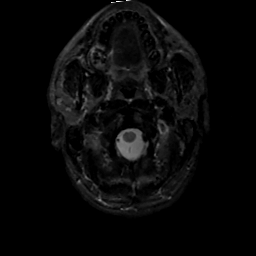

MR Study #2, February 17, 1991 -- Slice #1

[Home][Help][Clinical][Tour 1][Tour 2] Slice 1